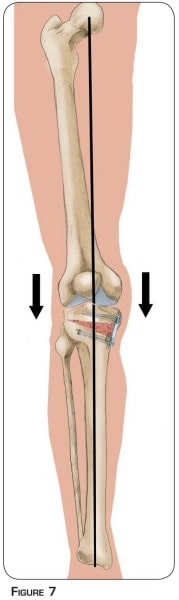

L’arthrose débutante interne est l’usure du cartilage présente entre la partie interne du fémur et du tibia (figure n°2 et photo n°1). La morphologie du membre inférieur en est souvent la cause principale. Sur une forme incurvée, tout le poids du corps passe plutôt par la partie interne du genou (figure n°3). Cette surcharge aboutit à l’usure prématurée du cartilage et du ménisque.